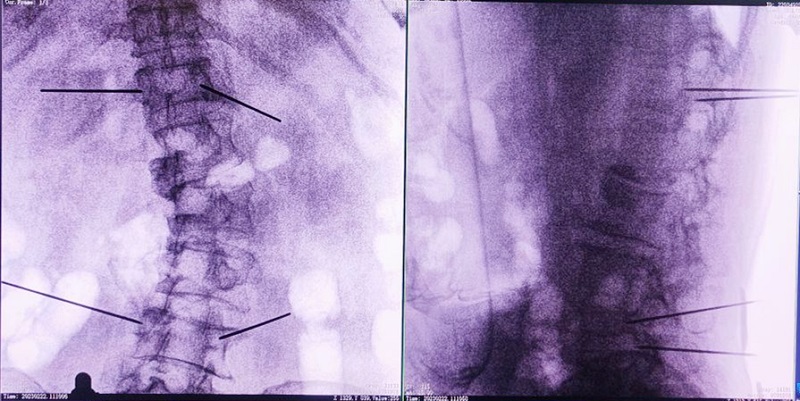

機器人輔助下椎體成形術,是以手術機器人智能機械臂為基礎,仿照經皮骨水泥椎體成形術的施術步驟,限定穿刺點、穿刺方向、角度和深度,使穿刺針經過安全路徑進入目標區域,然后進行骨水泥注入,輔助手術設計、精準指導手術實施。以普愛醫療的骨科手術機器人PL300B為例,其輔助進行的一例胸腰椎壓縮性骨折經皮椎體成形術的過程如下:

(1)首先使用普愛醫療三維C形臂采集胸腰椎病灶三維圖像,對傷椎進行三維重建;

(2)醫生制定個性化的手術方案,在機器人導航界面上進行路徑規劃;

(3)根據設定好的的位置和入針方向,植入引導針;

(4)所有引導針植入完畢后,沿引導針方向進行椎弓根及椎體置管,建立通道;

(5)沿通道注入骨水泥,恢復椎體高度,并觀察其擴散情況,達到滿意效果后,停止注入骨水泥。